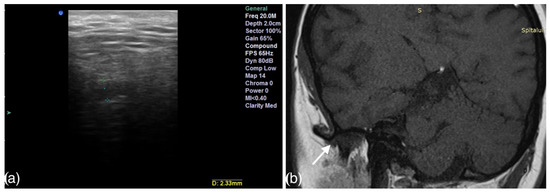

- Talmaceanu, D.; Lenghel, L.M.; Bolog, N.; Stanila, R.P.; Buduru, S.; Leucuta, D.C.; Rotar, H.; Baciut, M.; Baciut, G. High-resolution ultrasonography in assessing temporomandibular joint disc position. Med. Ultrason. 2018, 20, 64–70. [Google Scholar] [CrossRef] [Green Version]

- Talmaceanu, D.; Lenghel, L.M.; Bolog, N.; Buduru, S.; Leucuta, D.; Horatiu, R. High-resolution ultrasound imaging compared to magnetic resonance imaging for temporomandibular joint disorders: An in vivo study. Eur. J. Radiol. 2020, 132, 109921. [Google Scholar] [CrossRef]